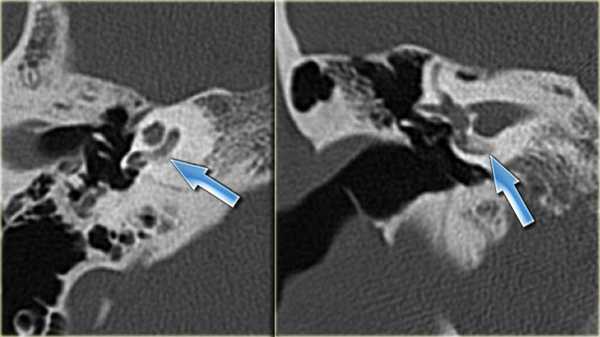

КТ-картина оссификации (обызвествления) лабиринта

Большое значение в постановке диагноза имеет проведение компьютерной томографии височной кости.

- МРТ и КТ височной кости. Компьютерную или магнитно-резонансную томографию назначаются для исключения других возможных поражений структур внутреннего уха: доброкачественных и злокачественных опухолей, аномалий развития, травматических повреждений. Иногда на снимках удается определить деформацию перепончатого лабиринта.